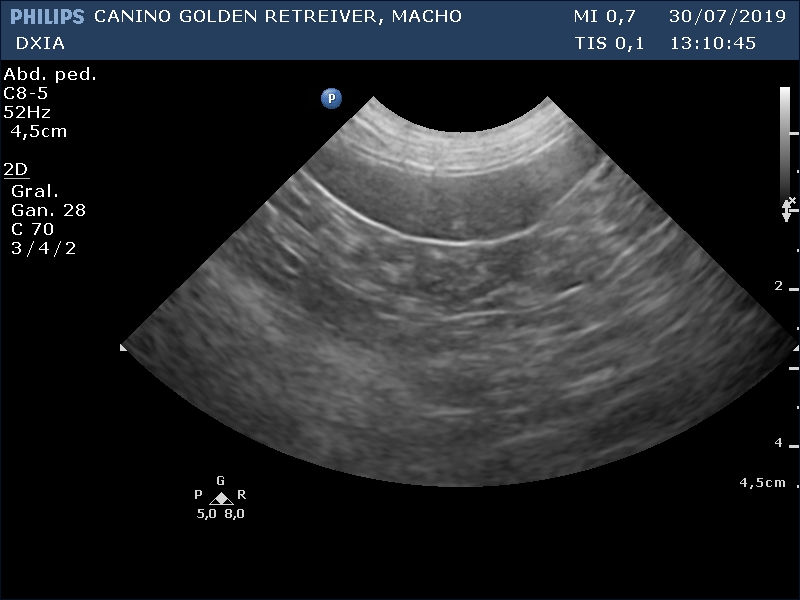

Durante los estudio ecográficos se observa marcada mejoría del parénquima hepática con reducción de la zona afectada y disminución de ese aspecto nodular observado en estudios previos.

Estas son varias imágenes obtenidas del parénquima hepático:

Última Imagen Hepática DXIA Scott

Última Imagen Hepática ante último ciclo de quimio